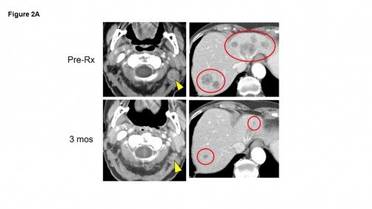

Photo Caption: For a patient whose Merkle cell carcinoma had spread to multiple organs, the treatment resulted in substantial tum